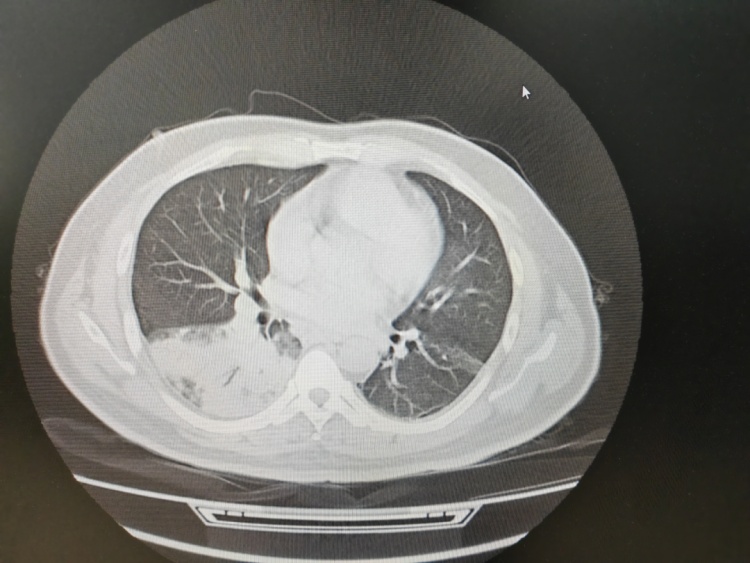

呼吸内科主任沈三英详细询问,并为患者完善了相应检查。结果显示,张先生的左肺竟然“白”了一大片。气管镜检查后,团队再通过肺泡灌洗液NGS检测抓住元凶——军团菌。